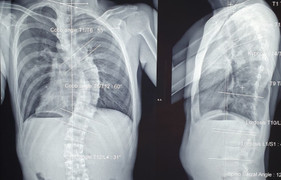

Bác sỹ trắng đêm chỉnh cột sống hình con rắn cho bé gái 13 tuổi

Cột sống cong vẹo hình con rắn khiến bé gái 13 tuổi đi lại, sinh hoạt khó khăn được các bác sỹ BV Bạch Mai (Hà Nội) nắn chỉnh thành công trong ca mổ xuyên đêm.